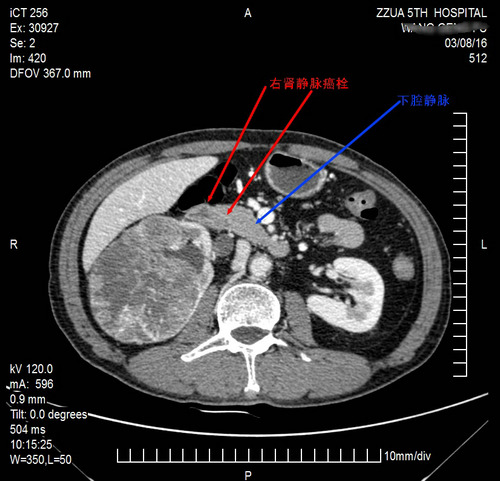

春回大地、万物复苏、孕育希望的时节,郑州大学第五附属医院泌尿外科迎来了一位来自豫北的病友王某。经病友介绍,王某辗转来到我院,满怀希望地找到邢东亮医生,要求做微创腹腔镜手术。邢大夫看完片子后头疼地对家属说:“病史8年,晚期转移性肾癌,瘤体巨大,即便是开放手术也是难度高,风险很大、建议病理穿刺活检后分子靶向治疗。”但家属不甘心,想争取哪怕是一线的手术机会。与患者家属沟通后,积极与医院放射影像科,超声科,血库等相关科室联系,着手进行充分的手术前准备,并作为重大手术上报医务科。检查中发现合并右肾静脉癌栓,已生长至下腔静脉入口处。术前邢东亮医生就该患者病情多次与北京解放军总医院、广州中山肿瘤医院及省内泌尿外科知名专家沟通交流诊疗意见及诊疗方案,一致认为按指南规范,可手术切除原发灶及左侧肾上腺转移灶,术后积极分子靶向治疗。还就防止术中癌栓脱落、是否防止腔静脉滤网问题,多次与医院血管外科副主任崔文军副主任医师沟通交流意见,并经过诊疗组及科内多次讨论,科主任酒涛主任医师,科副主任康郑军主任医师最后拍板,拟定由邢东亮医生主刀实施腹腔镜下右肾根治性切除+左侧肾上腺肿瘤切除术,术中阻断下腔静脉,完整切除癌栓。

2016年3月11日下午,在麻醉科主任胡强夫主任医师、麻醉师李霞医生,手术室护士长杨楠带领的护理团队协助下,由包括主刀医师邢东亮在内的康郑军诊疗手术团队顺利施术。按既定手术方案,先游离出右肾静脉及下腔静脉,处理肾动脉后,用腔静脉阻断钳部分下腔静脉阻断(约2/3),用直线切割闭合器沿肾静脉根部,连同约1/5的下腔静脉壁切除,完整切除右肾静脉癌栓,标本检查癌栓完整,然后翻身重新消毒把左侧肾上腺一并切除,耻骨上横切口方法,取出双侧标本。手术顺利,腔镜手术时间3小时27分钟,出血260ml。术中诊疗组长康郑军主任医师把控全局,悉心指导,包括朱海鹏主任医师、何江、王栋、张玉瑞主治医师在内的泌尿外科手术医师,就手术细节不断在台下出谋划策,主管医师于洋医师,术后拖着疲惫的身影回到病房,看到麻醉苏醒后的患者,感慨的说道:我们很疲惫,但很欣慰!主扶镜手何笑凯主治医师术后总结道:我们挑战手术极限,紧张中的坚持换来了最后胜利!

该类合并肾静脉、腔静脉癌栓的肾癌手术,手术难度大,手术过程复杂,风险高。目前国内仍以开放手术为主,省内仅有少数专家曾腹腔镜下或机器人辅助腹腔镜完成该类手术,郑州大学第五附属医院泌尿外科再次挑战了自身技术极限,标志着泌尿外科腹腔镜微创外科技术跻身省内前列!